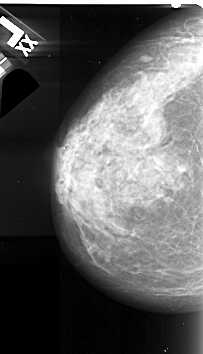

A_1058_1.LEFT_CC

LEFT_MLO LINES 5491 PIXELS_PER_LINE 3001 BITS_PER_PIXEL 16 RESOLUTION 42 NON_OVERLAY